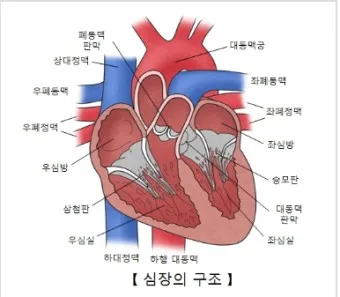

1. 심장 관련 원인

- 부정맥: 정상 심박수 범위 60-100회/분 이탈

- 심장 판막 이상: 증상 발현 시 심박수 변동 20% 이상

- 빈맥증: 휴식 시에도 심박수 100회/분 이상

- 서맥증: 심박수 60회/분 이하로 저하